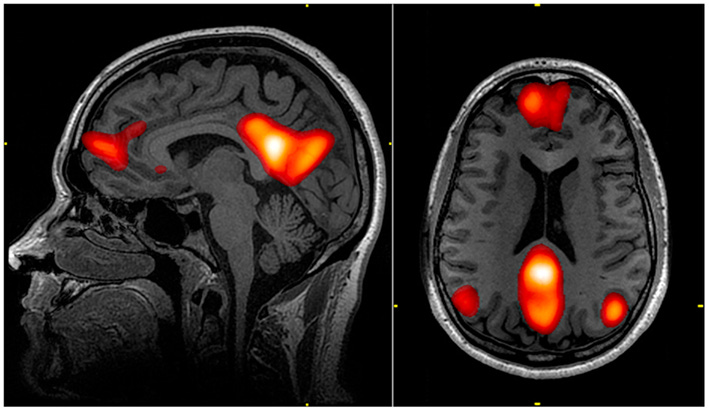

5/30: The Default Mode Network (DMN)

The DMN is central to this story and deserves its own entry. A note on networks: neuroscience has moved away from trying to figure out what specific brain regions do and toward figuring out network activity, because the brain is a complex system and regions don't work alone. There are a few large-scale brain networks that are in charge of most cognitive/experiential functions, and the DMN is an important one.

What does it do? You can find research linking it to a huge number of functions. Autobiographical thinking and daydreaming. Recalling our past, imagining our future, judging ourselves (and others), theory of mind, etc. It's been called "the wandering mind" network, because it's active when we aren't focused on our present environment. It’s related to the constant voice in your head that sounds like “you.” It also turns out, that it relates to unhappiness - a wandering mind is an unhappy mind, found Harvard psychologist's Daniel Gilbert.

It’s the central network of the narrative layer of the self. There have already been DMN subnetworks identified for different processes like relating to others, mind wandering, self evaluation, etc., and I’m sure many more are to come.

The DMN's discovery is an interesting story. With brain imaging studies, participants were usually put inside the MRI machine and asked to not do anything while a baseline was assessed (in order to be compare later to activity during a specific task so that "baseline activity" can be subtracted leaving only activity related to the task). It turns out, when asked to do nothing, the brain doesn't just turn off. A neuroscientist named Raichle noticed persistent network activity, and when he asked participants what they were doing, they'd say there were just, y'know, letting their minds wander - as anyone probably would if they were asked to not do anything. And of course mind wandering probably relates to you in some way (imagining the future, evaluating your past, thinking about what you need to do) appx. 90% of the time. This network activity was brighter (representing more activity) than anything the scientists were trying to actually measure in their studies. Turns out that daydreaming and thinking about ourselves, being very frequent activities, make well worn pathways in the brain, and these well-worn pathways become the resting states we default to most often.

The DMN's central node is called the Posterior Cingulate Cortex (PCC). It is usually the brightest spot in any brain. Again, while we don't think that any brain region acts in isolation, the PCC has been identified as a hub of self-reference. Neuroscientist Judson Brewer says its activity is related to "getting caught up" in our experience. So for example, rather than listening to someone speak, thinking about our perspective instead. Or instead of enjoying dancing, imagining how we look.